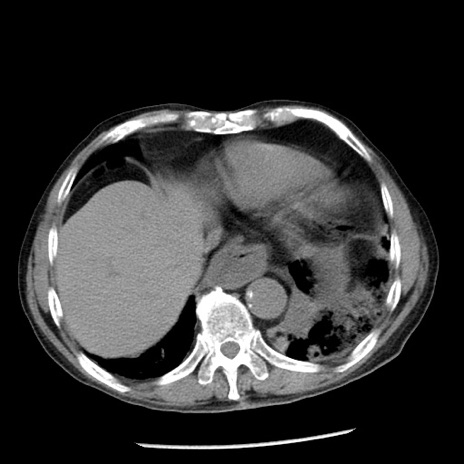

症例26(横断像)

【症例】80歳代男性

【主訴】嘔吐

【現病歴】昨晩2回嘔吐あり、今朝になっても嘔吐あり。来院。

【既往歴】胃潰瘍

【身体所見】意識清明、BT 37.6℃、BP 166/95mmHg、HR 100bpm、SpO2 97%、腹部:平坦・軟、腸蠕動音聴取良好、圧痛なし。

【データ】WBC 21900、CRP 1.46